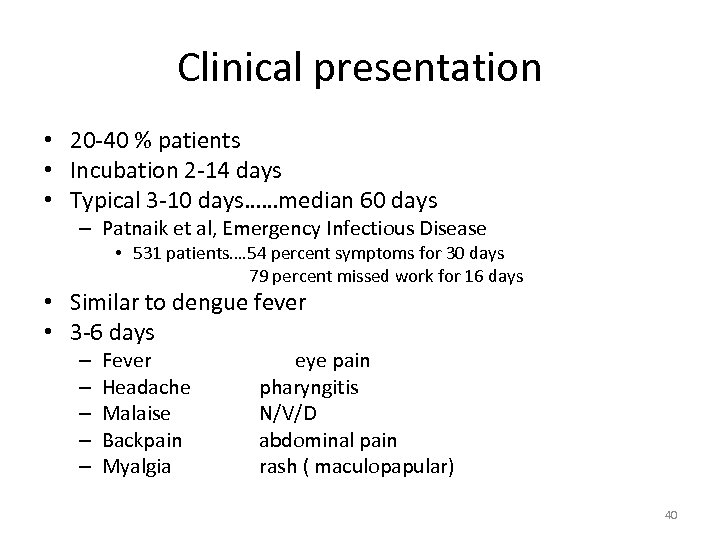

Clinical presentation • 20 -40 % patients • Incubation 2 -14 days • Typical 3 -10 days……median 60 days – Patnaik et al, Emergency Infectious Disease • 531 patients…. 54 percent symptoms for 30 days 79 percent missed work for 16 days • Similar to dengue fever • 3 -6 days – – – Fever Headache Malaise Backpain Myalgia eye pain pharyngitis N/V/D abdominal pain rash ( maculopapular) 40